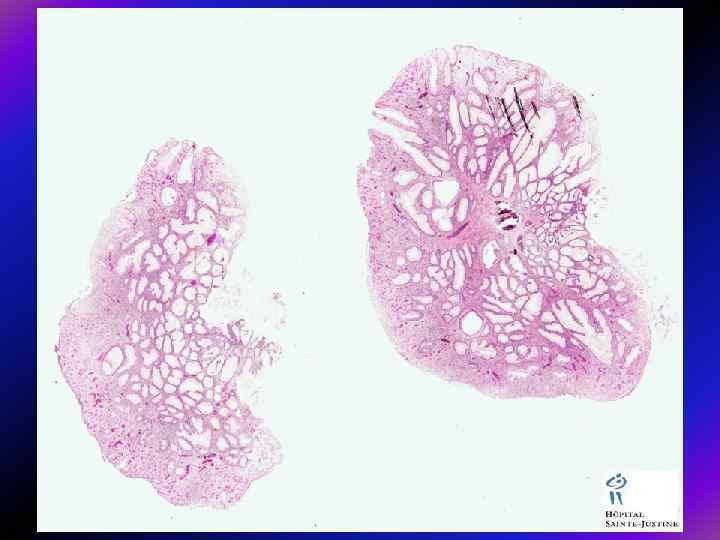

Морфологія поліпів • Як звичайно, аденоматозні поліпи поділяють на – тубулярні, – тубуло-вільозні і – вільозні (класифікація ВОЗ). Тубулярні аденоми трапляються найчастіше і становлять 75— 87% усіх аденом, тоді як тубуло-вільозні лише 8— 15%, а вільозні — 5— 10%. Тубулярні аденоми мають порівняно менші розміри: у дослідженні, проведеному в шпиталі Св. Марка, 76% тубулярних аденом були розмірами < 3 см, натомість лише 25% тубуло-вільозних і 14% вільозних аденом мали розміри до 1 см.

• У тубулярних аденомах проліферуючий епітелій формує прямі або розгалужені трубчасті структури з диспластичною тканиною, • а у вільозних — утворює видовжені пальцеподібні випинання, які складаються з диспластичного епітелію. • У тубуло-вільозних аденом змішана структура, де кожен тип структури повинен становити не менше 25% маси поліпа.

Тубулярна аденома Тубуло-вільозна аденома